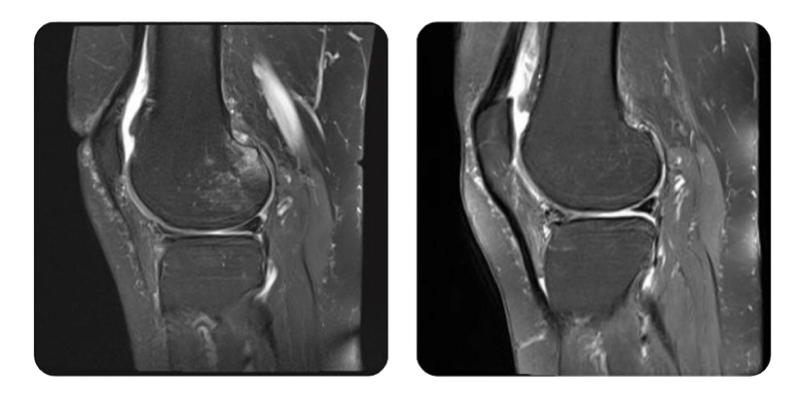

Prima

Dopo

V.B., 67 anni - Necrosi del condilo femorale laterale destro

- Frattura subcondrale con infossamento della regione postero-superiore del condilo femorale esterno.

Evoluzione: La paziente si e presentata per nuova valutazione clinica e strumentale dopo il primo ciclo di trattamento, composto da 20 sedute per necrosi del condilo laterale.

Prognosi: Dopo il trattamento non riferisce piu dolori significativi. Il dolore al ginocchio si e ridotto in modo importante, da 8/10 a 3/10.